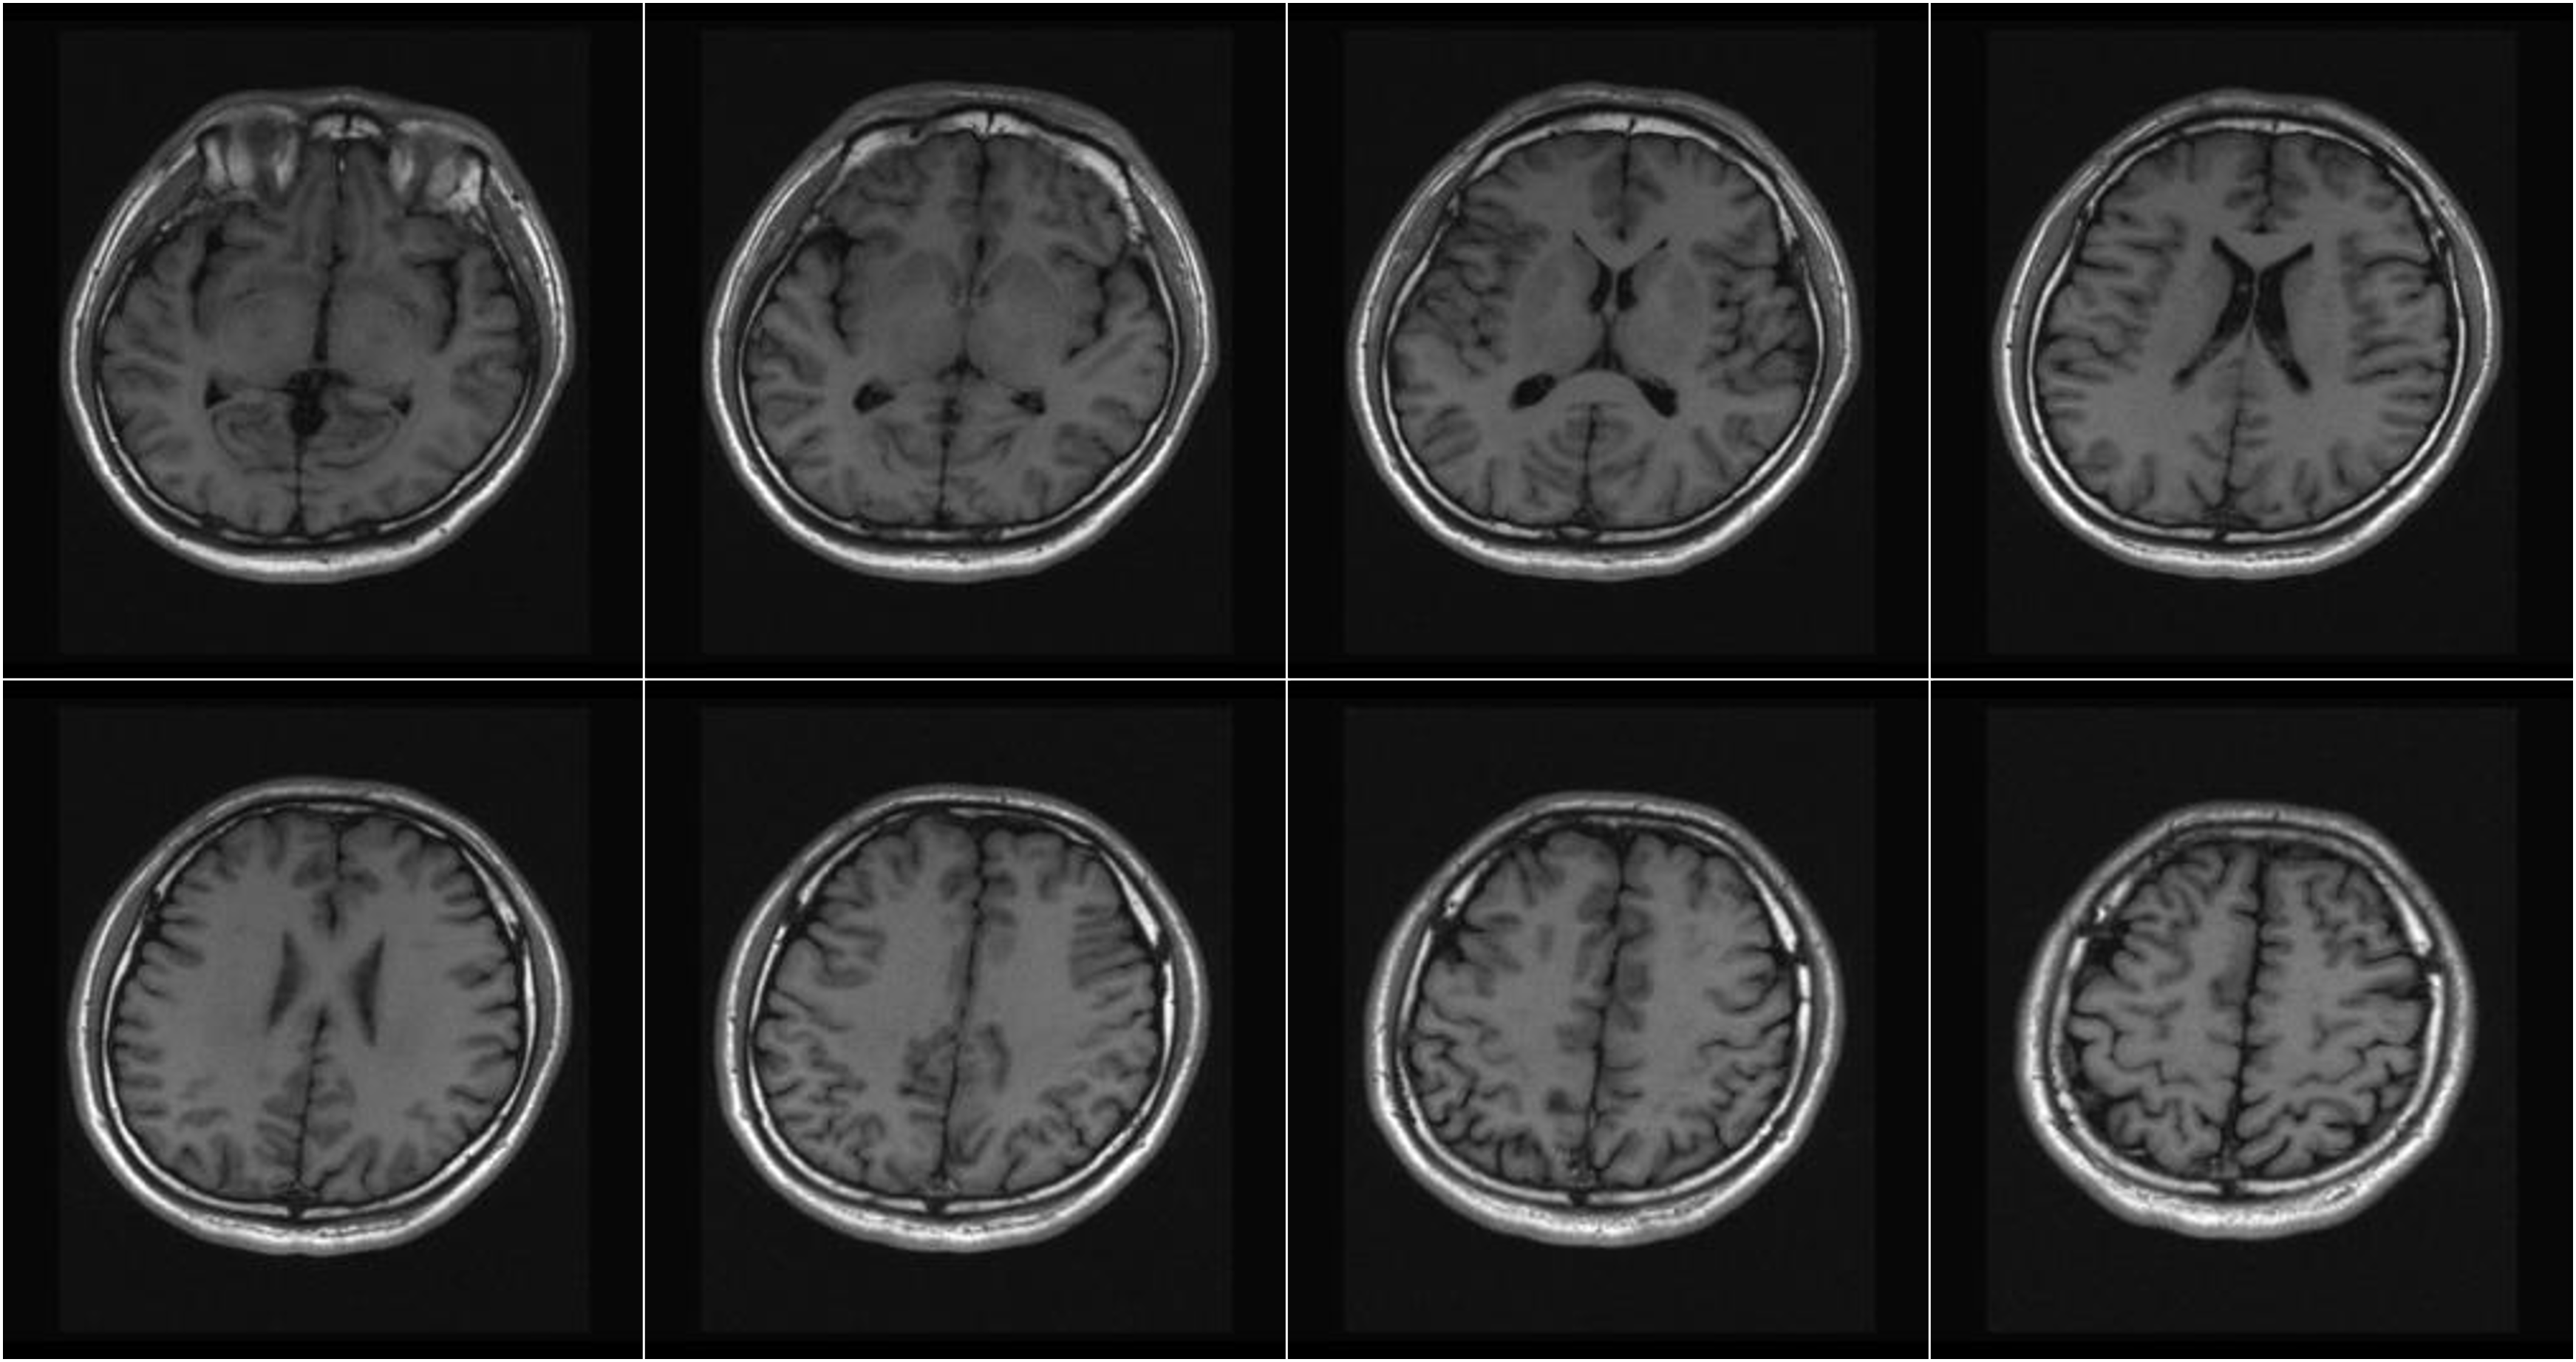

Hình ảnh lâm sàng